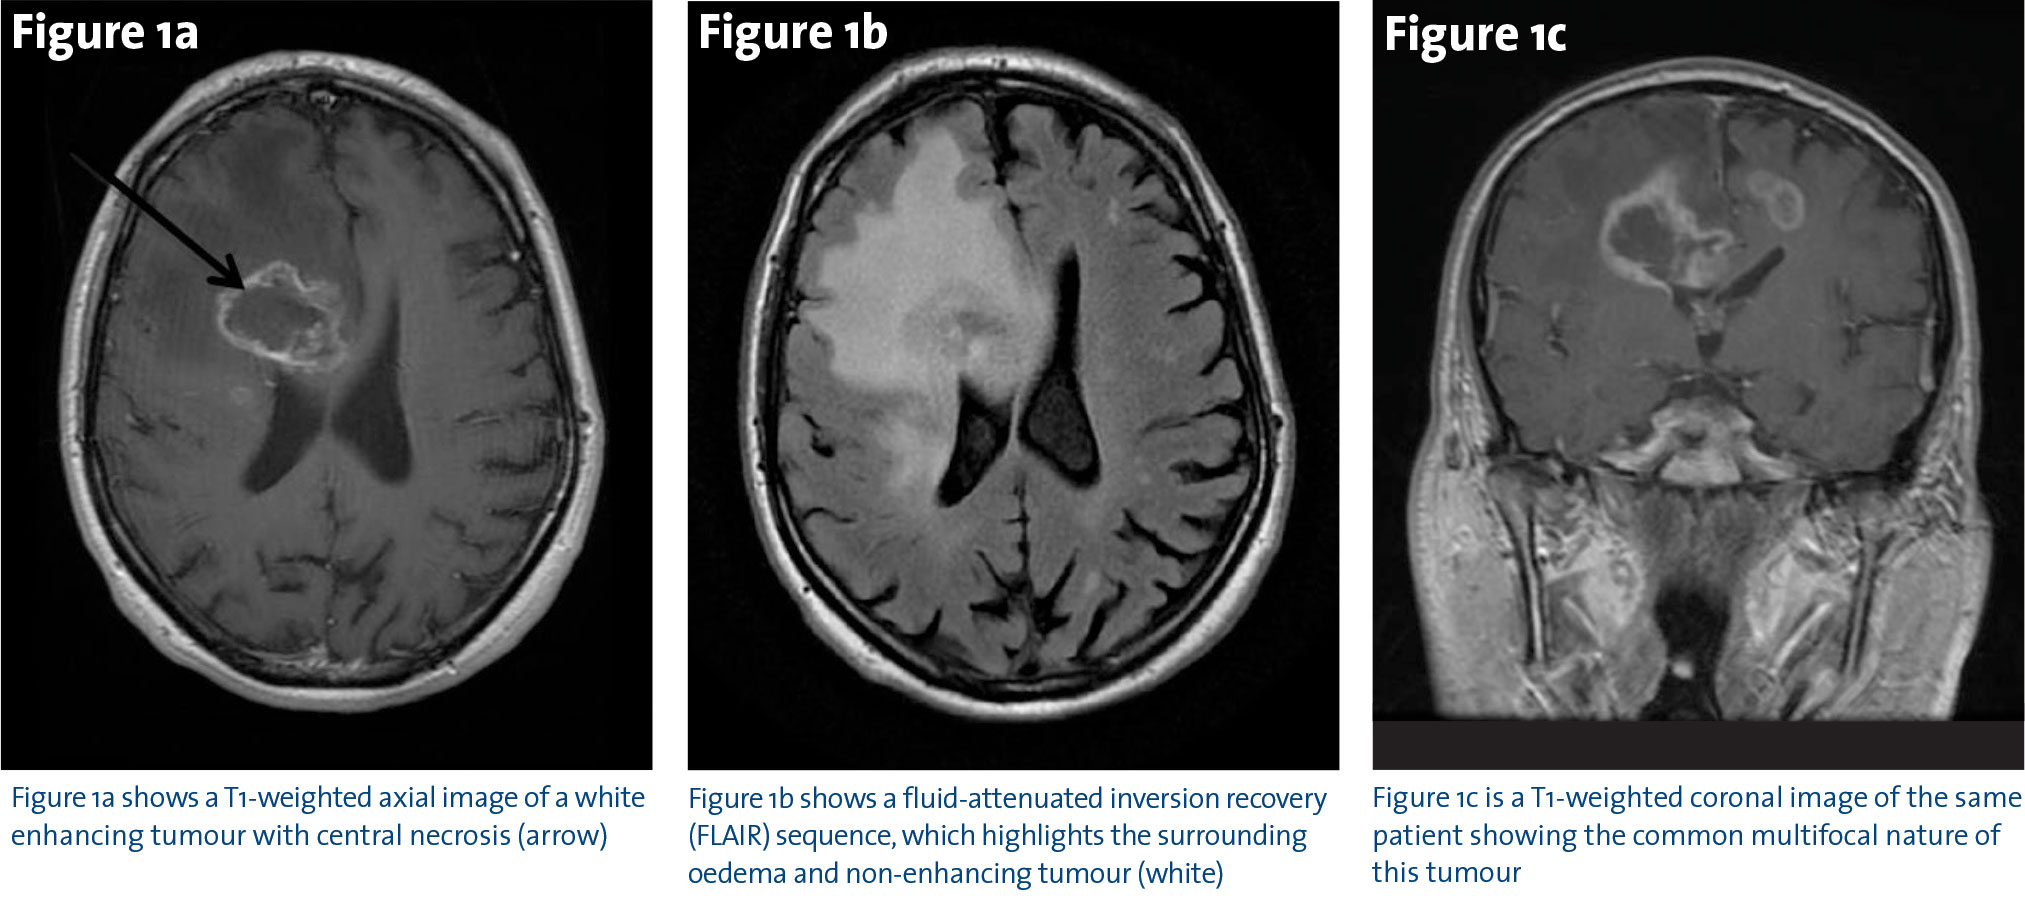

Most patients present with a short history of confusion, headaches and progressive neurological dysfunction depending on the tumour location. Magnetic Resonance Imaging (MRI) is the investigation of choice and typically shows a contrast-enhancing mass (Figure 1a), with extensive tumour-related oedema, which is best seen on Fluid-Attenuated Inversion Recovery (FLAIR) sequences (Figure 1b).

The standard course of treatment for GBM in accessible tumours is surgery followed by radiotherapy (RT) and chemotherapy ie. temozolomide. Surgery is usually diagnostic and therapeutic. Maximal resection without neurological compromise is the aim, but many tumours are multifocal (Figure 1c)